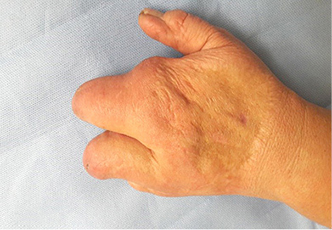

13 pav.  14 pav.

14 pav.

15 pav.

Atokieji rezultatai, praėjus maždaug 13 m. po rekonstrukcinių operacijų. Pacientės taip pat paprašyta parodyti, kaip sugeba suimti rašiklį. Nufotografuota donorinė dešinės pėdos vieta (13–15 pav.)